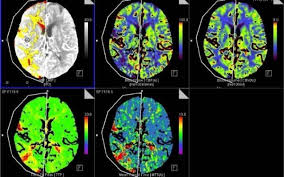

মস্তিষ্কে আক্রমণ করতে সক্ষম করোনা: গবেষণা

প্রাণঘাতী করোনা ভাইরাস মস্তিষ্কে সরাসরি আক্রমণ করতে সক্ষম। আর এর কারণে কিছু কিছু রোগী মাথা ব্যাথা, বিভ্রান্তিতে ভুগছেন। এর মধ্যে আবার কিছু রোগী মানসিক বিকারগ্রস্তও হয়েছেন। বুধবার প্রকাশিত একটি গবেষণায়